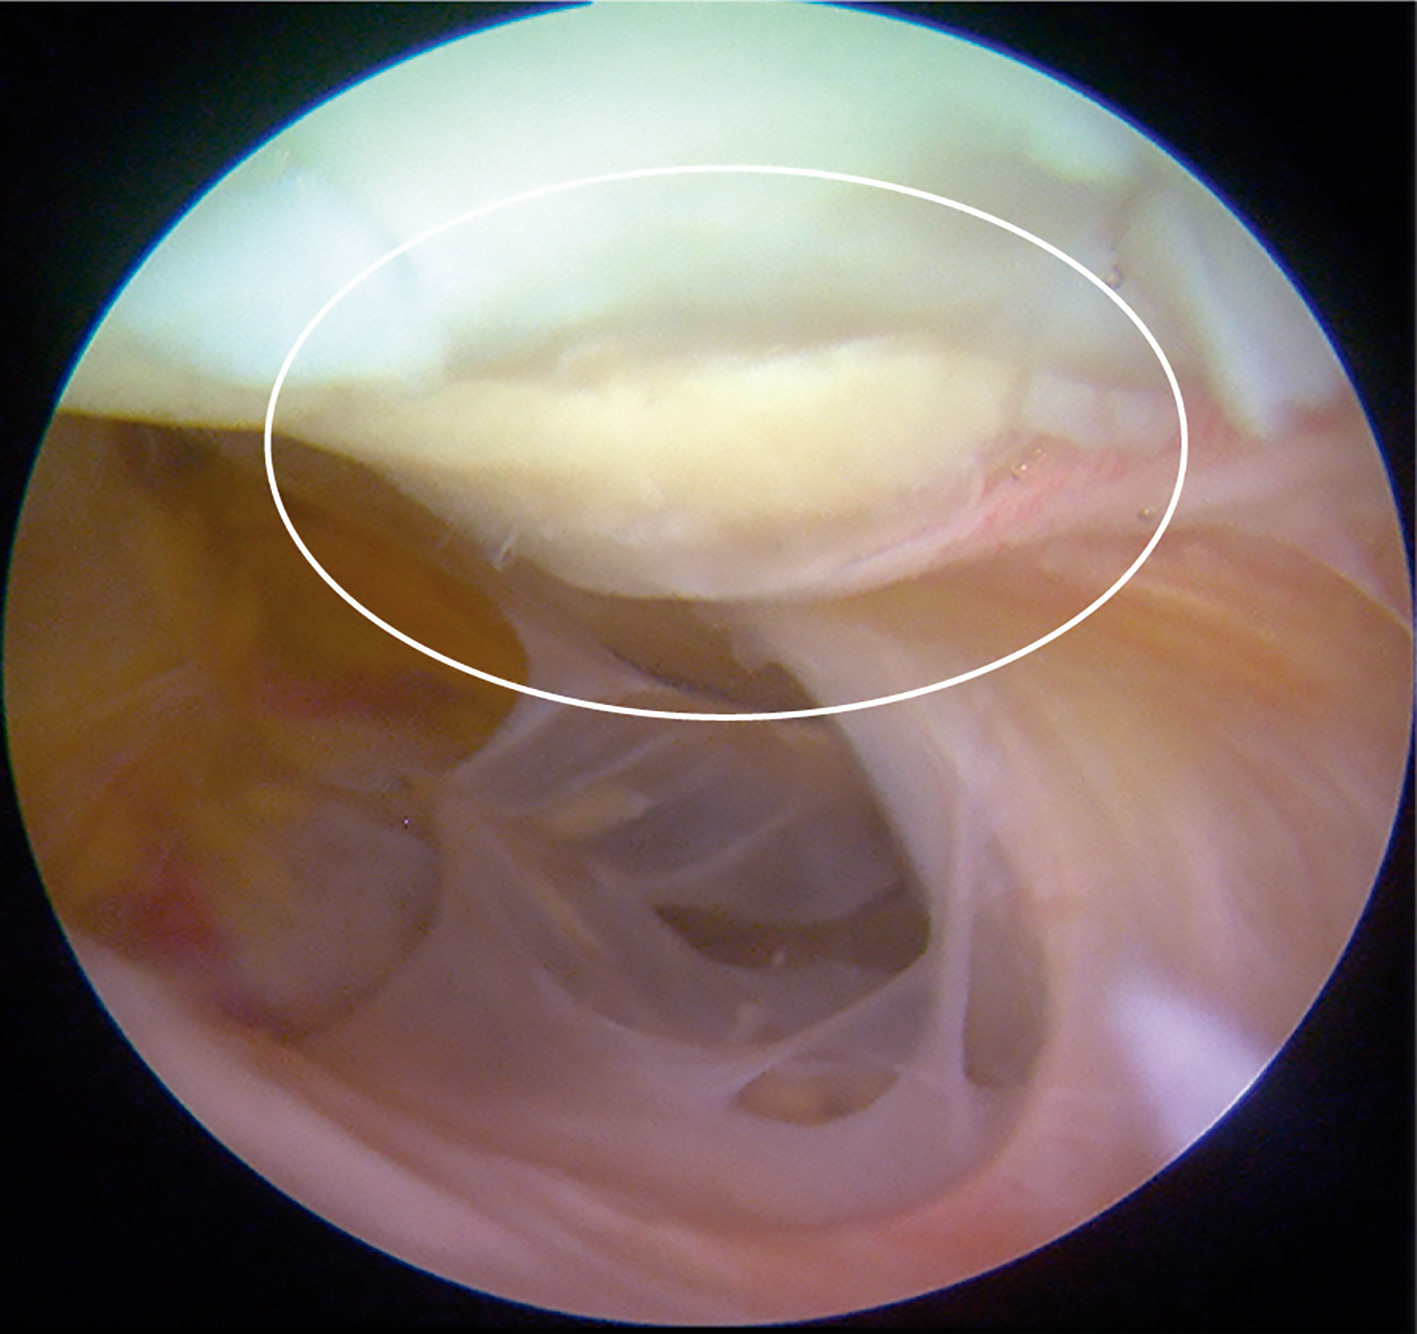

Evaluación de la segunda vista artroscópica

Un total de 9 pacientes accedieron voluntariamente a realizar una segunda vista artroscópica. En todos los casos el implante se observó integrado al tejido adyacente, de aspecto y consistencia similar al cartílago nativo. No observamos ningún caso de hipertrofia del implante. El valor promedio de la evaluación mediante la escala de la ICRS fue de 10,52 ± 0,23, siendo un valor muy cercano al máximo de dicha escala, que es de 12.

Figura 8. Segunda vista artroscópica. Se muestra el mismo constructo de la Figura 2C 1 año posterior a ser implantado. Se observan los bordes de la lesión integrados al tejido adyacente, así como integridad del implante.